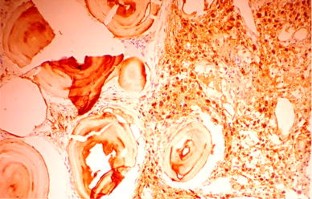

Primary localized amyloidosis in the head and neck region is a rare entity. The most commonly involved organ is larynx. Primary amyloidosis localized to the sinonasal tract is extremely rare. We report one such case along with a brief review of the associated literature. The aim of reporting this case is to emphasize the fact that sometimes nasal amyloidosis can also present with signs and symptoms of nasal and nasopharyngeal malignancy. The definitive diagnosis in such cases depends upon histopathology and further confirmed by immunohistochemistry. A 55-year old male presented with recurrent episodes of nasal bleed, bilateral nasal obstruction, and bilateral hearing loss from last 7 years. On clinical examination a mass was found in the nasal cavity on both sides reaching up to the nasopharynx. Contrast enhanced CT scan revealed that the mass was extending up to the skull base and destroying bony landmarks of the nasal cavity and paranasal sinuses. Mass was proved to be amyloidosis after histopathological examination. It showed multiple blotches of globular submucosal deposit of amyloid, on staining with Congo red. Immunohistochemistry confirmed AL amyloidosis with expression of mixed kappa and lambda light chain immunoglobulin (κ > λ). No evidence of systemic amyloidosis was found after proper work up. It was managed by conservative surgery.